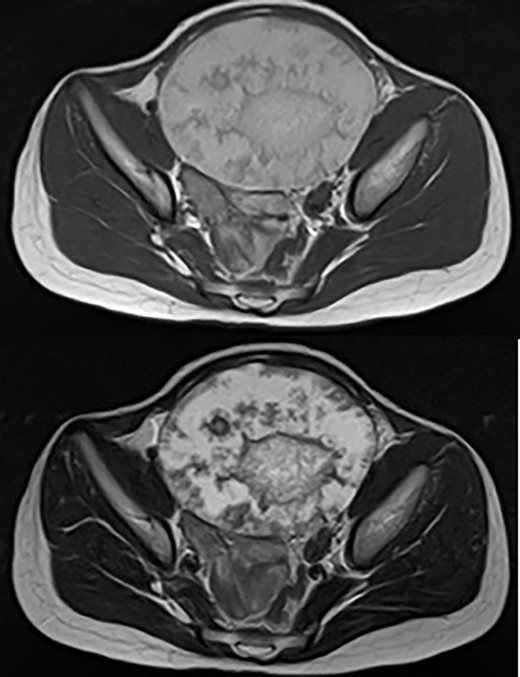

The patient was a 10-year-old girl. She visited our hospital after her grandmother noticed a mass in her lower abdomen that she had been aware of for 6 months. Abdominal ultrasonography revealed that she had a large mass centered in her lower abdomen. The tumor border was clear, the internal structure was heterogeneous and the blood flow was poor (Fig. 1). We suspected an ovarian tumor, but blood tests showed no elevated tumor markers such as AFP and CA19–9. Abdominal magnetic resonance imaging revealed a cystic mass 10 cm in diameter with high intensity on T1-weighted images and high intensity on T2-weighted images (Fig. 2). Abdominal computed tomography revealed a spleen near the navel and a cystic lesion with poor contrast that continued from the lower pole of the spleen (Fig. 3).

Abdominal ultrasonography revealed a large mass centered in her lower abdomen. The tumor border was clear, the internal structure was heterogeneous and the blood flow was poor.

Abdominal magnetic resonance imaging revealed a cystic mass 10 cm in diameter with high intensity on T1-weighted images (upper) and high intensity on T2-weighted images (lower).